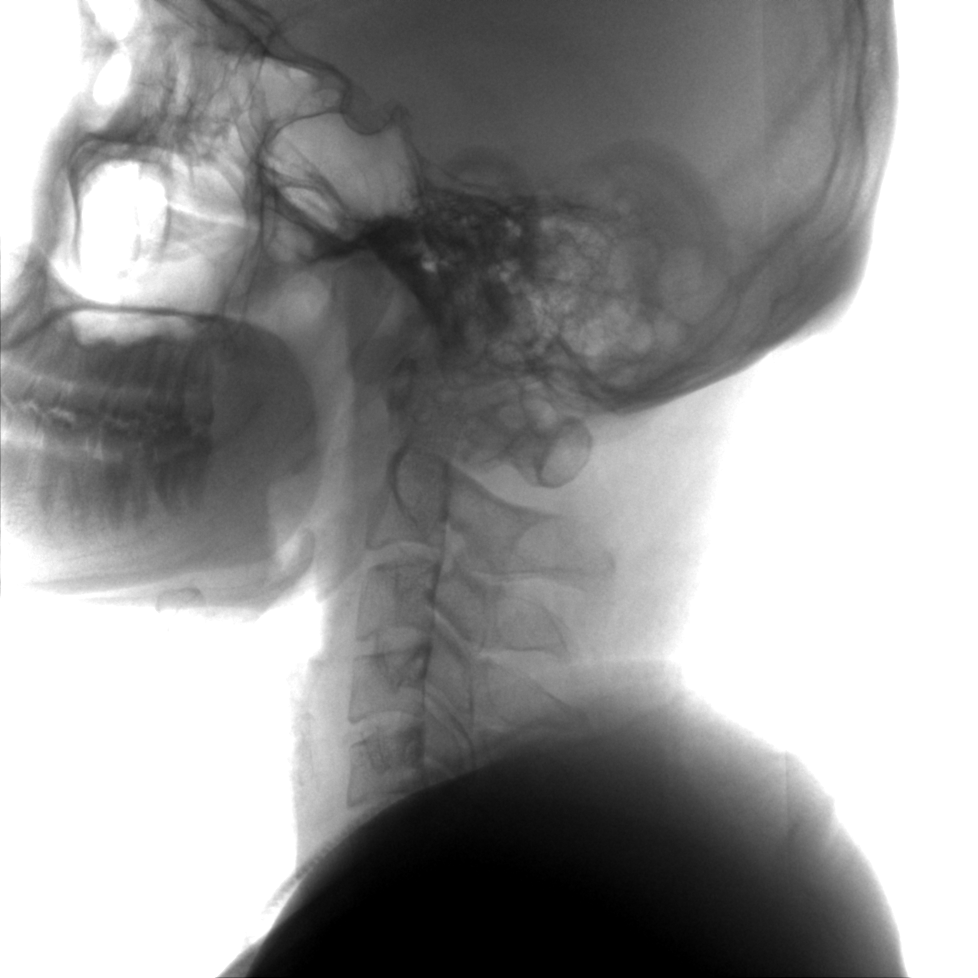

成像清晰、操作簡易、擺位便捷,主要適用于骨科、脊柱外科、矯形外科、創(chuàng)傷骨科及手術(shù)室等,能大幅度提升手術(shù)水準(zhǔn),降低手術(shù)風(fēng)險(xiǎn)和并發(fā)癥的概率。

提供更大的術(shù)中三維成像視野,采集更多圖像信息,可一次拍全全段頸椎、全段腰椎、七節(jié)胸椎、雙側(cè)骶髂關(guān)節(jié)、股骨頭及單側(cè)盆骨。